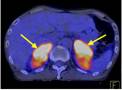

Ca lâm sàng 1: Bệnh nhân Vũ D.L., nam, 56 tuổi. Chẩn đoán: Non-Hodgkin Lymphoma , GPB: WF7.

Hình PET/CT toàn thân thấy tổn thương hạch ở nhiều vị trí: vùng cổ, trung thất, hố nách, ổ bụng, bẹn (các mũi tên)